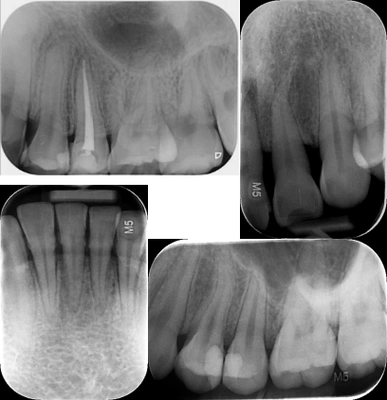

根尖片医疗辐射是人类接触电离辐射的最主要来源,x线,ct,放射治疗都会